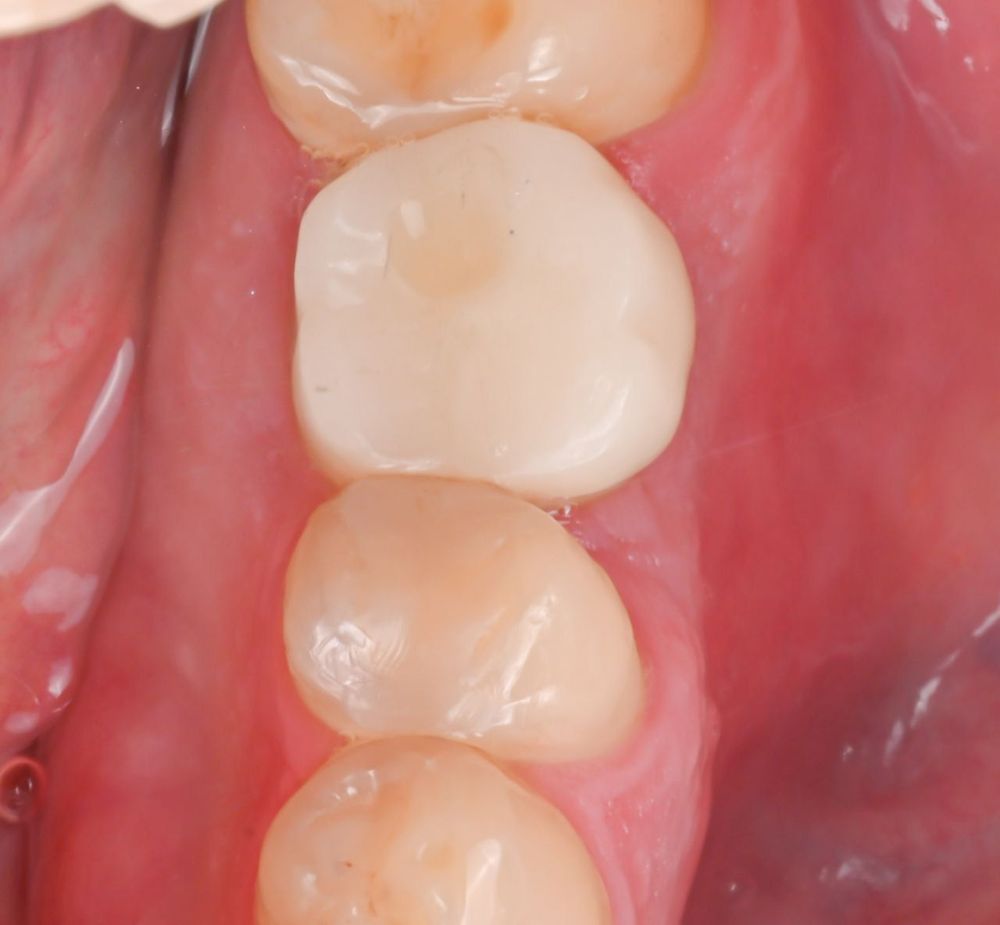

По прошествии трёх месяцев, после подтверждённой остеоинтеграции и стабилизации мягких тканей, формирователь был извлечён, и выполнено изготовление временной коронки. Ещё через месяц, при отсутствии воспаления и при полной готовности тканей, была проведена финальная реставрация: установка постоянной ортопедической конструкции на имплантат.